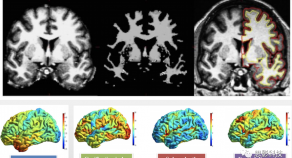

核磁數(shù)據(jù)處理

思影科技腦結(jié)構(gòu)磁共振成像數(shù)據(jù)處理業(yè)務(wù)

2020-06-02